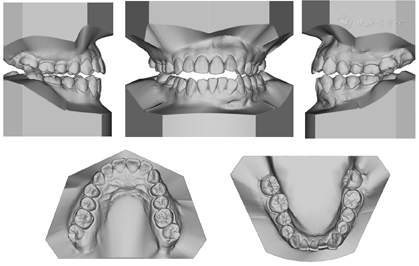

(6)正畸术前模型分析:上颌牙列拥挤度3 mm,下颌牙列拥挤度5 mm;Bolton比:前牙比79.6%,全牙比92.2%;Spee曲线曲度1.5 mm;上牙弓后段宽度46.8 mm,下牙弓后段宽度41.0 mm(图4)。